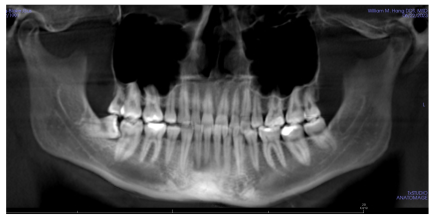

Panoramic x-ray

- Missing Teeth: Missing U&L 4’s

- Other Problems: Still has wisdom teeth, LR8 mesially inclined